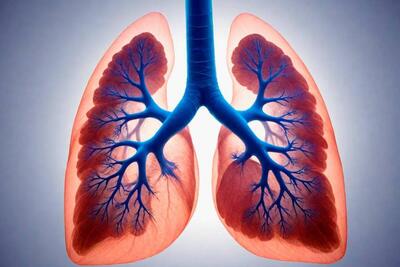

عفونت ریه

بازیگر کوتاه قامت ایران بدلیل عفونت ریه و خون در بخش مراقبت های ویژه بستری شد .

یک مطالعه جدید در مقیاس کوچک نشان میدهد که مه مغزی ناشی از سندرم کووید طولانی مدت ممکن است به دلیل اختلال در عملکرد ریه به دنبال عفونت یک فرد باشد.

دربار پادشاهی عربستان از تکمیل آزمایش های پزشکی پادشاه این کشور پس از ابتلا به عفونت ریه و بهبودی وی خبر می دهد.

به گزارش دیوان سلطنتی عربستان سعودی، ملک سلمان بن عبدالعزیز، پادشاه ۸۸ ساله این کشور، به دلیل ابتلا به عفونت ریه تحت بررسیها و آزمایشهای پزشکی قرار گرفته است.

نوزادان به دلیل رشد ناکافی عضلات مری ممکن است دچار رفلاکس اسید شوند که منجر به تف کردن و استفراغ، امتناع از تغذیه، مشکل در خواب و رشد و عفونتهای مکرر ریه میشود.

این واکسن عفونتهای خون و مغز و ریه کودکان را کاهش میدهد

واکسن پنوموکوک میتواند عفونتهای خون، مغز، ریه و.. را در سطح کشور به میزان قابل توجهی کاهش دهد، طبق برنامه واکسیناسیون جدید ۳ دز آن در ۲، ۴ و ۱۲ ماهگی به نوزادان تزریق میشود.

چراغ سبز FDA به یک داروی استنشاقی نانویی برای عفونتهای باکتریایی ریه

اصفهان- بیدار شدن غول خفته گاوخونی یعنی فاجعه اقتصادی و اجتماعی، یعنی کانونهای ریزگردی که امروز چشم و ریه دیار زنده رود را پر کرده و فردا بیشک ۱۴ استان از جمله پایتخت را درگیر خواهد کرد.